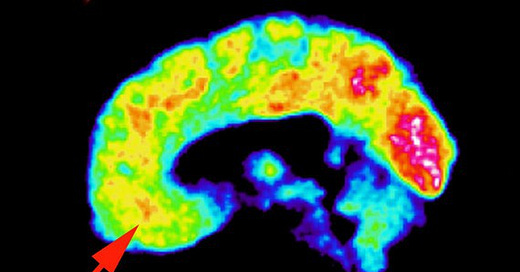

However, the same argument cannot be made for psychopathy. Psychopathy is genetic, it is not environmental. What changes in a psychopathic person based on environmental triggers is behavior, not the psychopathy itself. Regardless of how a psychopath is raised, they are born psychopathic, and psychopathy will remain. Environment and abuse can create a very badly behaving psychopath, but won’t make them more or less psychopathic. Scan the brain of a noncriminal psychopath, and you will see what I mean;